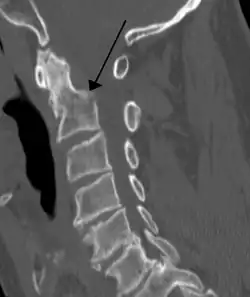

A fracture of the base of the dens as seen on plain X-ray -

A fracture of the base of the dens as seen on CT -